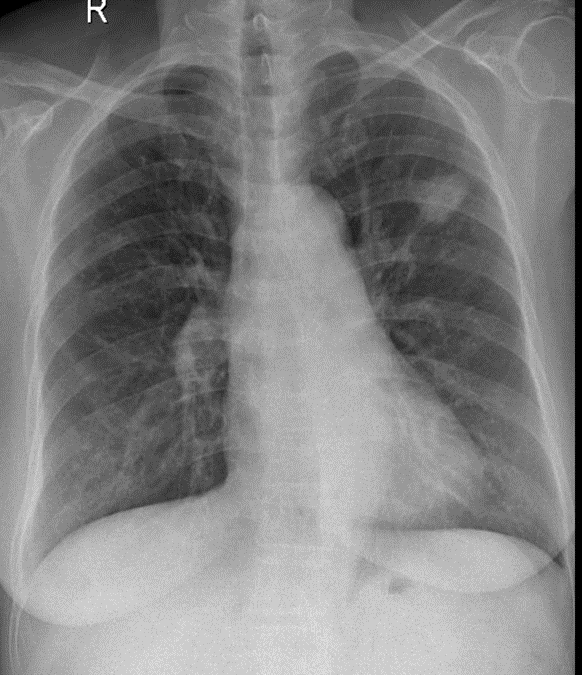

Hãy phân tích tình huống nữ 65 tuổi

1-U thùy trên phổi (T)